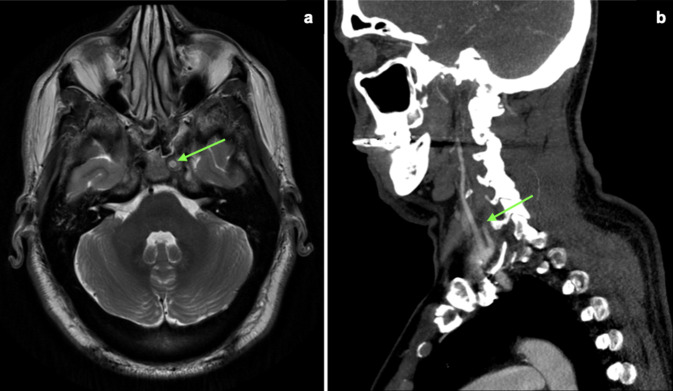

A 56 year old male presented in our clinic complaining of daily headaches with progressive severity during the last 6 months. The headaches usually occurred in the morning, although particularly painful episodes could wake him up at night. His medical history was only remarkable for a seat belt injury from a car accident ten years before the beginning of the symptoms. As part of the diagnostic work-up, a brain MRI was performed revealing loss of normal flow void in the left internal carotid artery (ICA) suggesting proximal occlusion (Fig. 1a).

Fig. 1.

Apparent internal carotid artery (ICA) occlusion. a MRI (T2-weighted, axial plane) showing loss of normal flow void in the left ICA (green arrow) suggesting proximal occlusion. b CT-angiography with abrupt attenuation of flow within the left ICA (green arrow) indicating complete occlusion